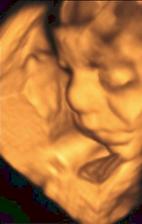

14.10.08 poradna - odebrána krev+moč-výsledky za 14dní, mimísek má 4cm a dostali jsme TĚHOTENSKOU PRŮKAZKU🙂)).............................................27.10.08 poradna - mimísek má 6,5cm, genetický test v naprostém pořádku, riziko se snížilo na 1/9050 - takže téměř žádné-huráááááááá!............................................. 19.11.2008 odběry krve na triplle testy v 16tt - negativní🙂))............................................. 16.12.2008 poradna - vše v pořádku.............................................18.12.2008 velký ultrazvuk - mimísek je v naprostým pořádku, srdčko i všechno ostatní funguje jek má🙂)))............................................. 13.1.2009 poradna + test na cukr............................................. 27.1.2009 poradna - cokrovka je negativní, můžeme mlsat dál🙂............................................. 13.2.2009 4D ultrazvuk-mimísek se nám pořád skovával za ručičky, ale nakonec jsme ho přemluvili a aspoň na chvilku se nám ukázal🙂)............................................. 17.2.2009 poradna- prcek už je hlavičkou dolů a připravenej jít ven, navíc mi strašně tvrdne břicho takže mi dr. zvýšil dávku magnézia a musíme ležet............................................. 2.3.2009 velký ultrazvuk v 31tt - prcek je v pořádku a už má 1700g ............................................. 17.3.2009 poradna - vše ok, prcek má 2100g ............................................. 18.3.2009 sepsání porodopisu ............................................. 26.3.2009 nástup na mateřskou🙂